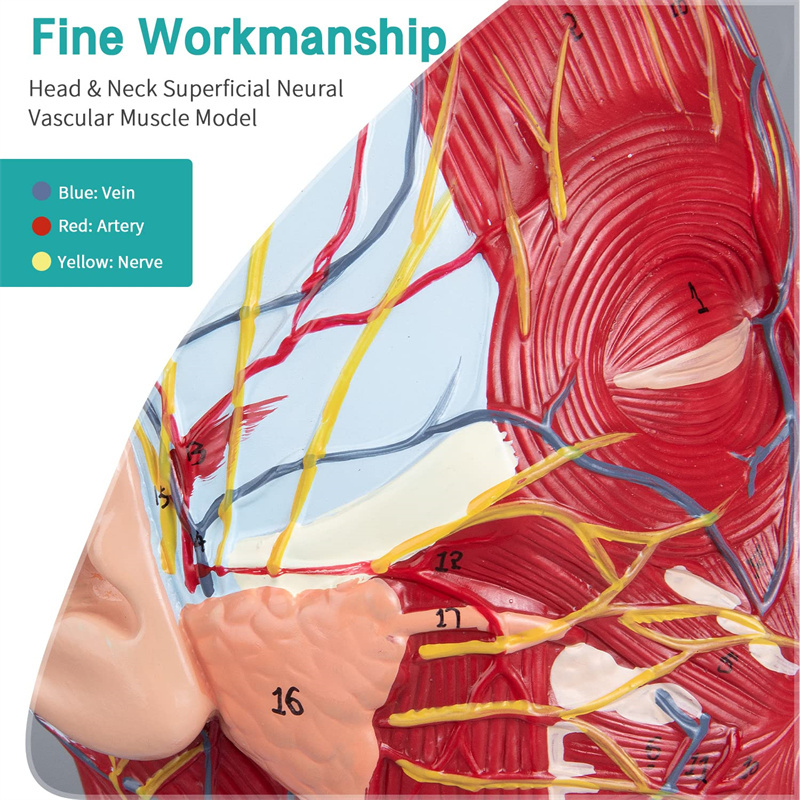

【Model otot neurovaskular cetek】 Sangat terperinci, nombor yang ditandai, telinga boleh dilepaskan, memperdalam pemahaman otot, kapal, saraf dan struktur dalaman kepala & leher. Red-artery, biru-vein, kuning-saraf.

【Ciri -ciri】 Ia menunjukkan otot -otot cetek muka yang terdedah; saluran darah cetek & saraf muka & kulit kepala; struktur dalaman kelenjar parotid & saluran pernafasan atas; Struktur keratan rentas sagittal tulang belakang serviks.

Model ini adalah model otot neurovaskular yang besar dan leher yang besar, 1 komponen, menunjukkan butiran kepala kanan dan leher manusia dan bahagian sagittal median, termasuk otot -otot dangkal yang terdedah pada muka, kapal cetek muka dan skalp, saraf, saraf, saraf, saraf, saraf, saraf, saraf, saraf, saraf, saraf, saraf, saraf, saraf, saraf, saraf, saraf, saraf, saraf, saraf, saraf, saraf, saraf, saraf, saraf, saraf, saraf, saraf, saraf, saraf, saraf, saraf, saraf, saraf, saraf, saraf, dan struktur medial kelenjar parotid dan saluran pernafasan atas, dan struktur bahagian sagittal tulang belakang serviks